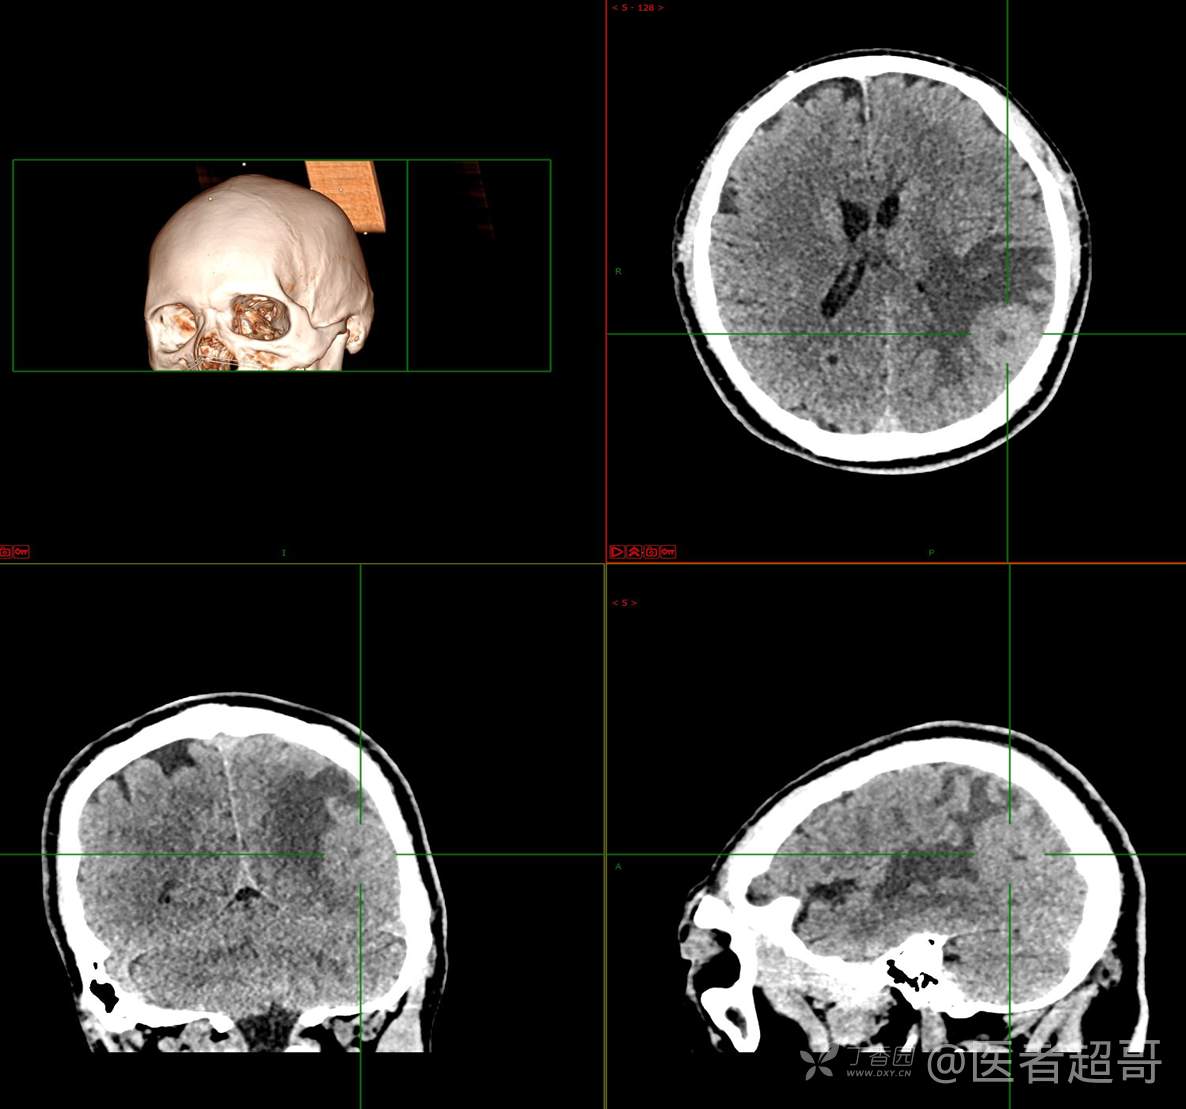

比较典型病例,CT、MRI齐全,请分析,领丁当!

男,56岁

主 诉:查体发现颅内占位10天。

现病史:患者于约10天前于我院查体时行颅脑MRI提示左侧顶叶占位病变,无头痛头晕,无恶心呕杜,无肢体活动不利,无感觉异常,现患者为求进一步治疗,就诊于我科门诊,门诊以“颅内占位性病变”收入我科。患者自发病以来,神志清,精神可,饮食及睡眠差,大小便无明显异常,体重无明显变化。